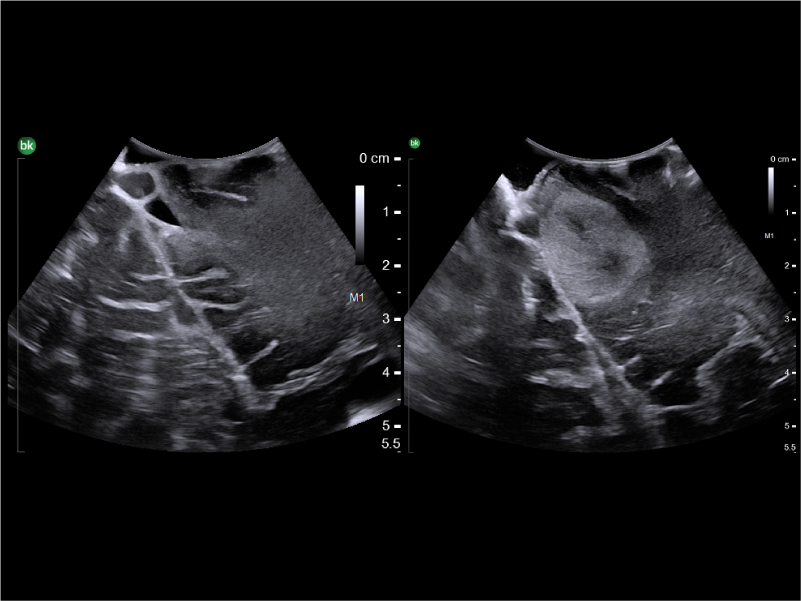

REAL-TIME VISUALIZATION HAS NEVER LOOKED THIS GOOD

- Monitor Progress: Compare live images with previous scans simultaneously using Dual Live Compare, Picture in Picture, or Stored Image Compare.